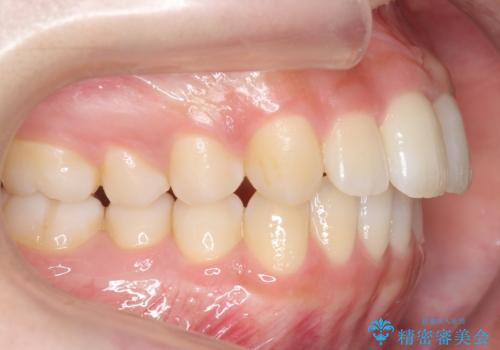

歯を抜かない矯正 出っ歯を抜かずに大きく下げることは可能です。

- 出っ歯を主訴に来院。

上の歯を全体に大きく後ろに下げる治療計画を立てました。

後ろに下げるために、親知らずは抜歯しています。

後ろに下げるために、ワイヤー矯正の前にカリエールという装置を使用しました。